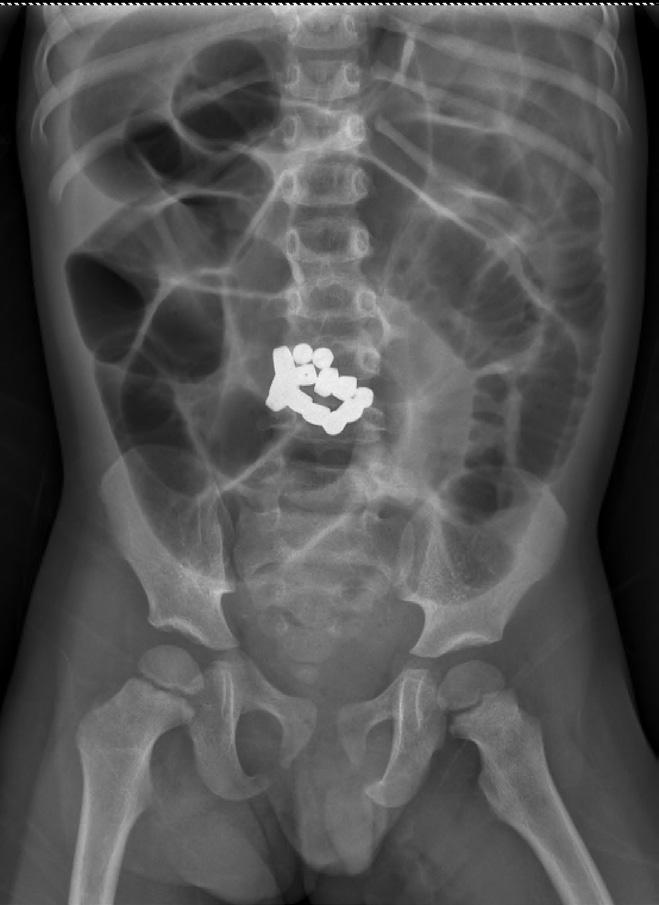

Ingestion de corps étranger par les enfants : épidémiologie, facteurs de risque et prise en charge